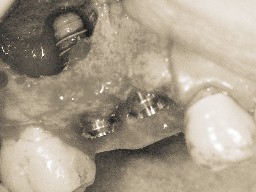

手術自体は局所麻酔+鎮静法(点滴麻酔)で何のお痛みも無く受けていただく事ができます。個人差はございますが、術後のお痛みも通常の抜歯程度で、術後数日で落ち着いてきます。入院の必要も無く、翌日から通常の生活をしていただけます。

これらのミスは術後初期段階に症状として出現することがあります。このような場合には埋入したインプラント(フィクスチャー)を抜去し、増骨手術など必要な処置の後に2~3ヶ月後に再手術を行います。